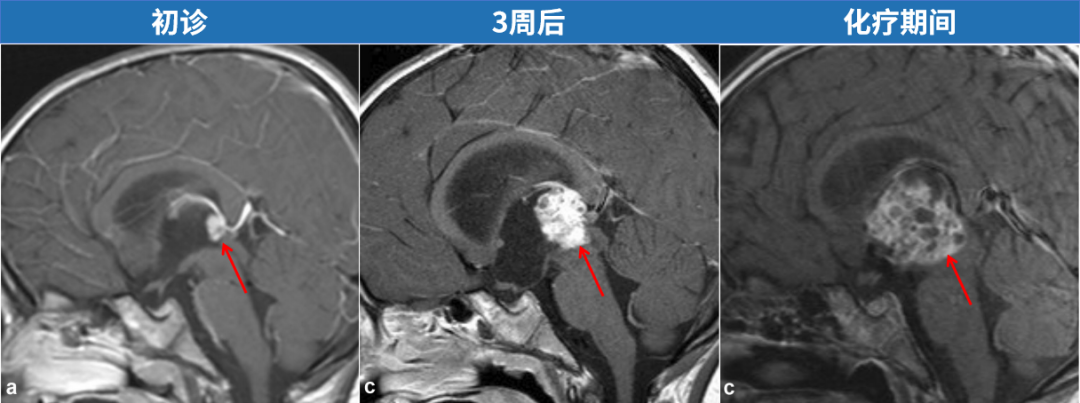

核磁共振图像上的一个微小白点被疏忽,导致一名国外男童几近病危,开颅手术中所见情形令医疗团队倍感震惊。该白点的临床意义何在?对于患者KK的家人而言,这引发了长达数月的忐忑历程,期间死神多次逼近这名5岁患儿,尽管化疗、外科手术及新型疗法相继应用,其颅内怪异肿瘤不仅未受抑制,反而呈现进行性增大。

5岁患儿KK作为家庭核心关爱对象,不幸出现健康问题。初始症状包括头痛与癫痫发作,家属携其就医后,头部核磁共振检查仅发现左侧额颞部存在蛛网膜囊肿,而位于第三脑室的一个小白点被漏诊,这成为后续一系列不良事件的起点。10日后,KK症状无改善,因剧烈头痛和呕吐再次入院,但本次未行影像学复查,仅通过腰椎穿刺排除脑膜炎后即出院。不料8天后病情急速加重,复查核磁显示原被忽视的小白点已发展为致命性病变——引发导水管梗阻和脑积水。

确诊后立即启动治疗方案。医疗团队尝试放置脑室外引流管,并通过脑脊液检测明确诊断为恶性生殖细胞肿瘤。因当地资源有限,KK被转至上级医疗中心,医生首先移除外引流管,实施内镜下第三脑室造瘘术(ETV)及隔膜造口术,成功控制脑积水。然而,原发肿瘤仍构成严重威胁,故迅速给予两个疗程化疗,但影像监测显示肿瘤持续生长,并阻塞双侧室间孔,经多学科讨论后行脑室腹腔分流术作为抢救措施。更令人担忧的是,后续2个月内即使接受大剂量化疗和干细胞移植,肿瘤体积依然增加。